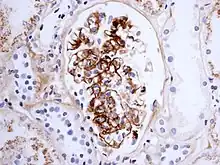

If there is doubt about the cause of the skin lesions, a biopsy of the skin may be performed to distinguish the purpura from other diseases that cause it, such as vasculitis due to cryoglobulinemia; on microscopy the appearances are of a hypersensitivity vasculitis, and immunofluorescence demonstrates IgA and C3 (a protein of the complement system) in the blood vessel wall.[4] However, overall serum complement levels are normal.

Biopsy of the kidney may be performed both to establish the diagnosis or to assess the severity of already suspected kidney disease. The main findings on kidney biopsy are increased cells and Ig deposition in the mesangium (part of the glomerulus, where blood is filtered), white blood cells, and the development of crescents. The changes are indistinguishable from those observed in IgA nephropathy.[9]